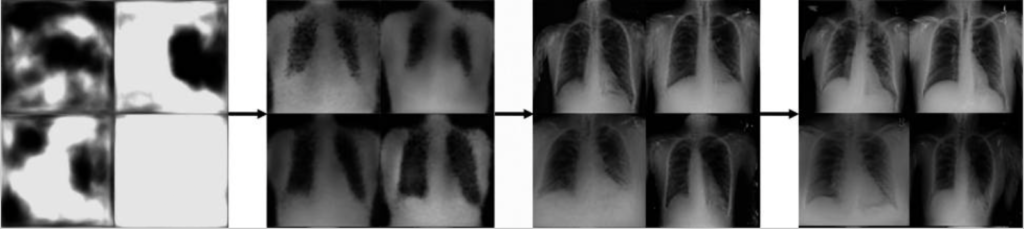

图1. 长达14小时的生成式人工智能模型的渐进式输出,产生假的胸部X射线。(来源:《未来医疗》杂志)

- 像生成式对抗网络(GANs)这样的生成式人工智能算法在真实的病人数据上进行训练

- 生成式人工智能模型生成与输入数据相似的新图像(如图1所示),但由于数据量或多样性的增加,可以产生更好的机器学习效果

- AI模型在合成数据上进行训练